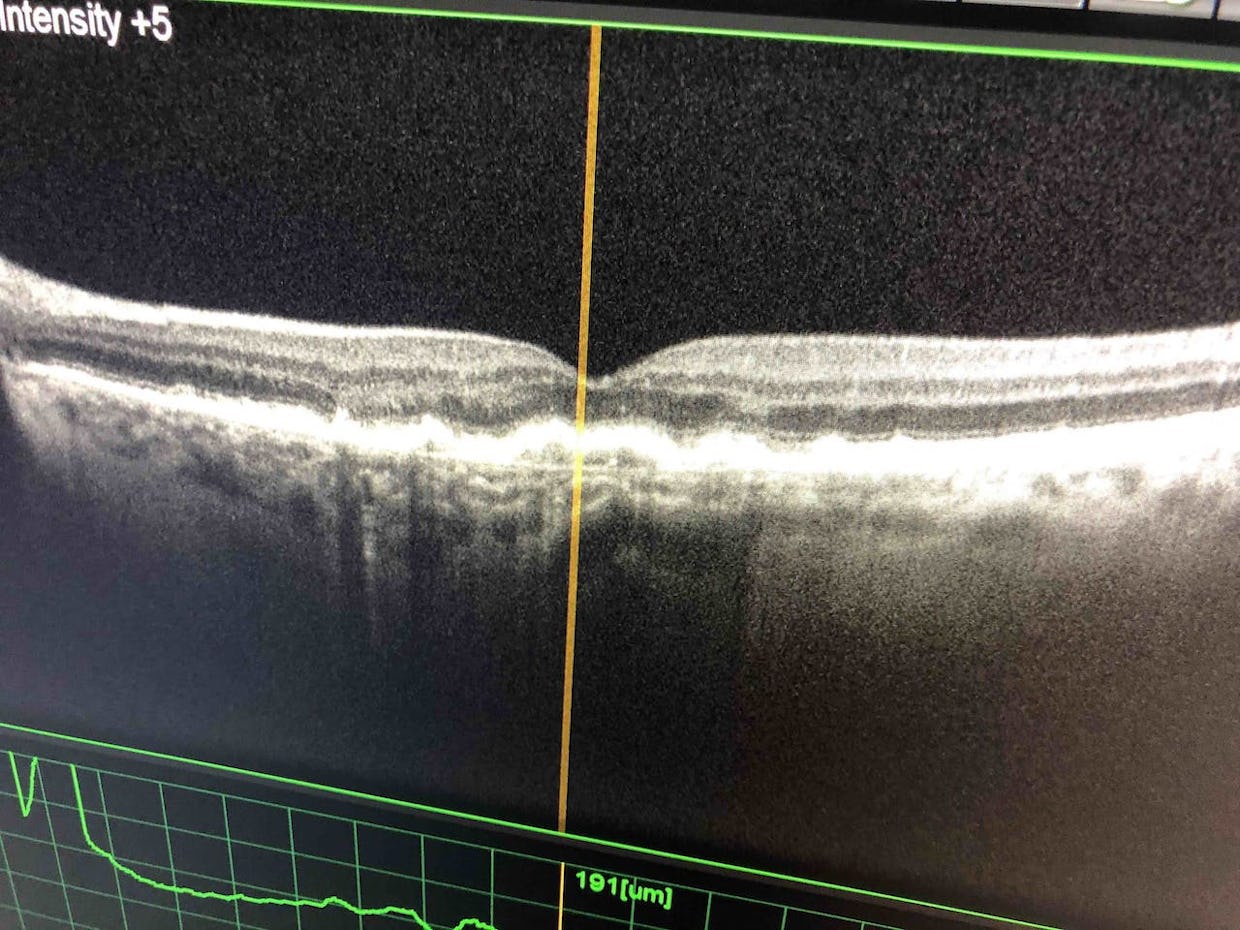

La clinique possède les équipements ultra-modernes nécessaires à la consultation allant de la simple visite de contrôle à la préparation des opérations pour tout type de chirurgie en passant par le suivi de toutes les maladies des yeux.